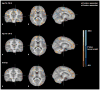

Results: Infant ε4 carriers had lower MWF and GMV measurements than noncarriers in precuneus, posterior/middle cingulate, lateral temporal, and medial occipitotemporal regions, areas preferentially affected by AD, and greater MWF and GMV measurements in extensive frontal regions and measurements were also significant in the subset of 2- to 6-month-old infants (MWF differences, P < .05, after correction for multiple comparisons; GMV differences, P < .001, uncorrected for multiple comparisons). Infant ε4 carriers also exhibited an attenuated relationship between MWF and age in posterior white matter regions.